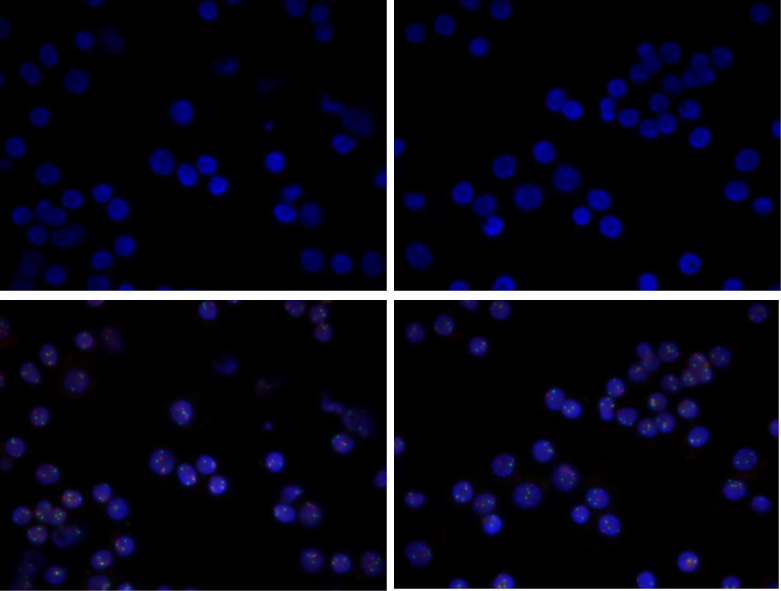

2. FISH杂交实验结果

使用CD138分选磁珠从1–2 mL新鲜骨髓样本(保存于2–8℃,不超过24小时)中富集CD138细胞。随后使用针对多发性骨髓瘤(MM)的FISH检测套餐对富集后的细胞进行遗传学分析。

该套餐包括一个用于检测1号染色体异常的1q探针,以及一个双色探针组合(红色标记D13S319位点,绿色标记LSI 13q34位点),用于同步评估13号染色体相关异常。

图2. 新鲜骨髓样本FISH检测结果

检测结果显示,CD138阳性细胞富集效率较高,荧光信号清晰、背景干扰低,异常信号模式(2R3G)的阳性率为86%,表明可对多发性骨髓瘤细胞进行有效检出。